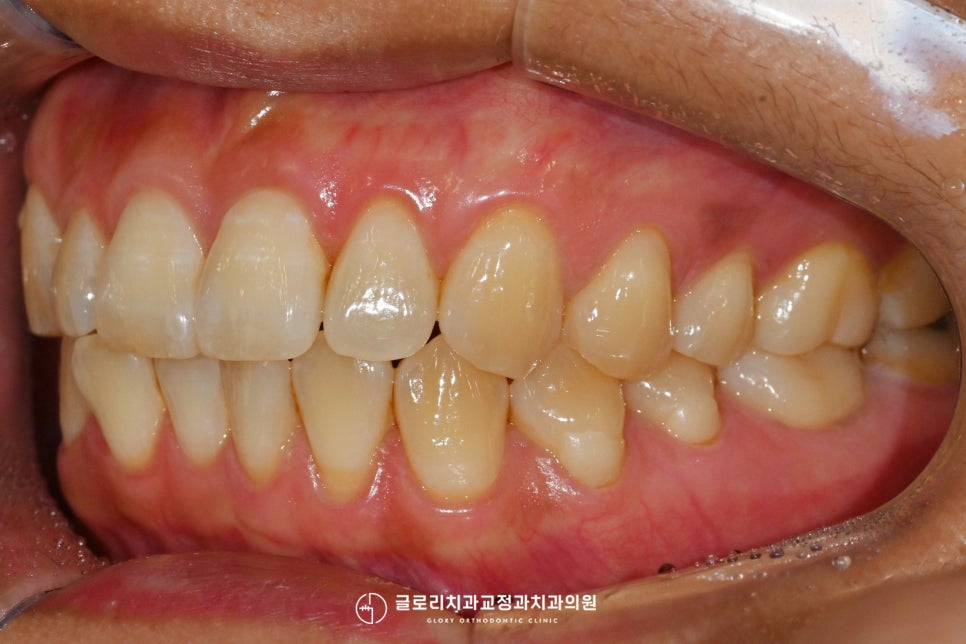

『치아 정출이란

이렇게 아래 대합 되는 이가 없을 경우

본래 위치에서 벗어나

더 많이 자라 나온 형태를 말하는데요.』

특히 임플란트 크라운을 제작할 경우

배열과 교합에 문제를 만들어 낼 수 있어

그에 맞는 조치가 필요합니다.